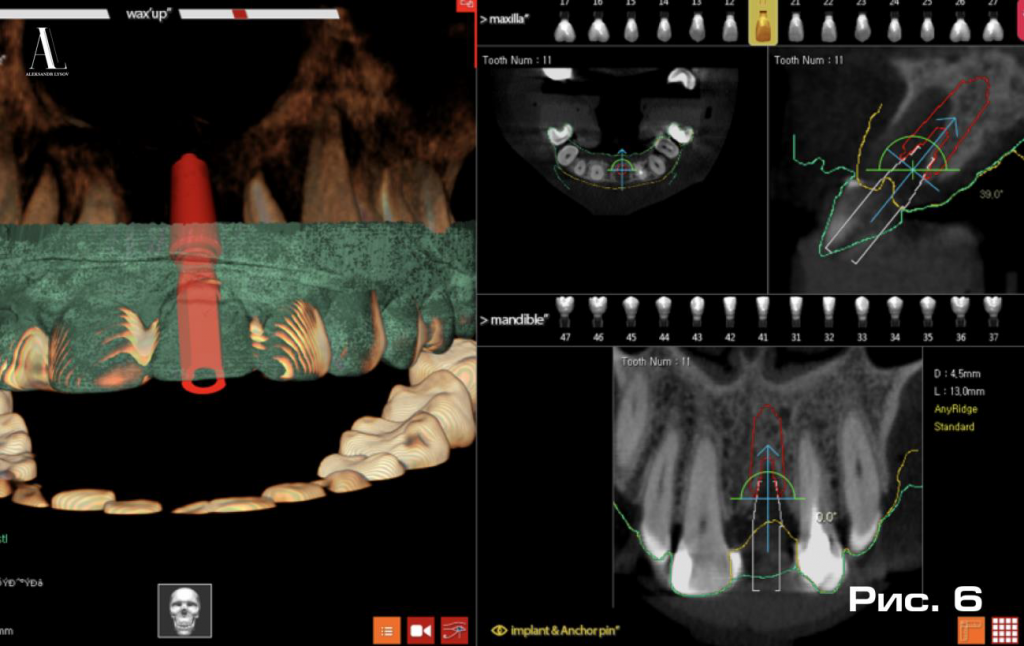

С помощью программы R2GATE (Megagen) выполнили трехмерное позиционирование имплантата (Рис. 6).

На следующем этапе с виртуально-установленного имплантата получили виртуальный слепок, который в виде модели со скан-абатментом был направлен в цифровую зуботехническую лабораторию. Благодаря возможности установки имплантата в строго запланированном положении и возможности програмировать расположение его антиротационного элемента, в нашем случае шестигранника, в лаборатории с использованием технологии CAD/CAM был изготовлен индивидуальный постоянный абатмент и временная коронка для него. Параллельно с этим был создан проект хирургического направляющего шаблона, который распечатали с помощью 3D принтера. В результате подготовительных работ были получены следующие материал: имплантат AnyRidge (Megagen), диаметром 4.5 мм и длинной 13 мм, направляющий хирургический шаблон, индивидуальный постоянный абатмент (далее - одномоментный абатмент) и временную коронку.